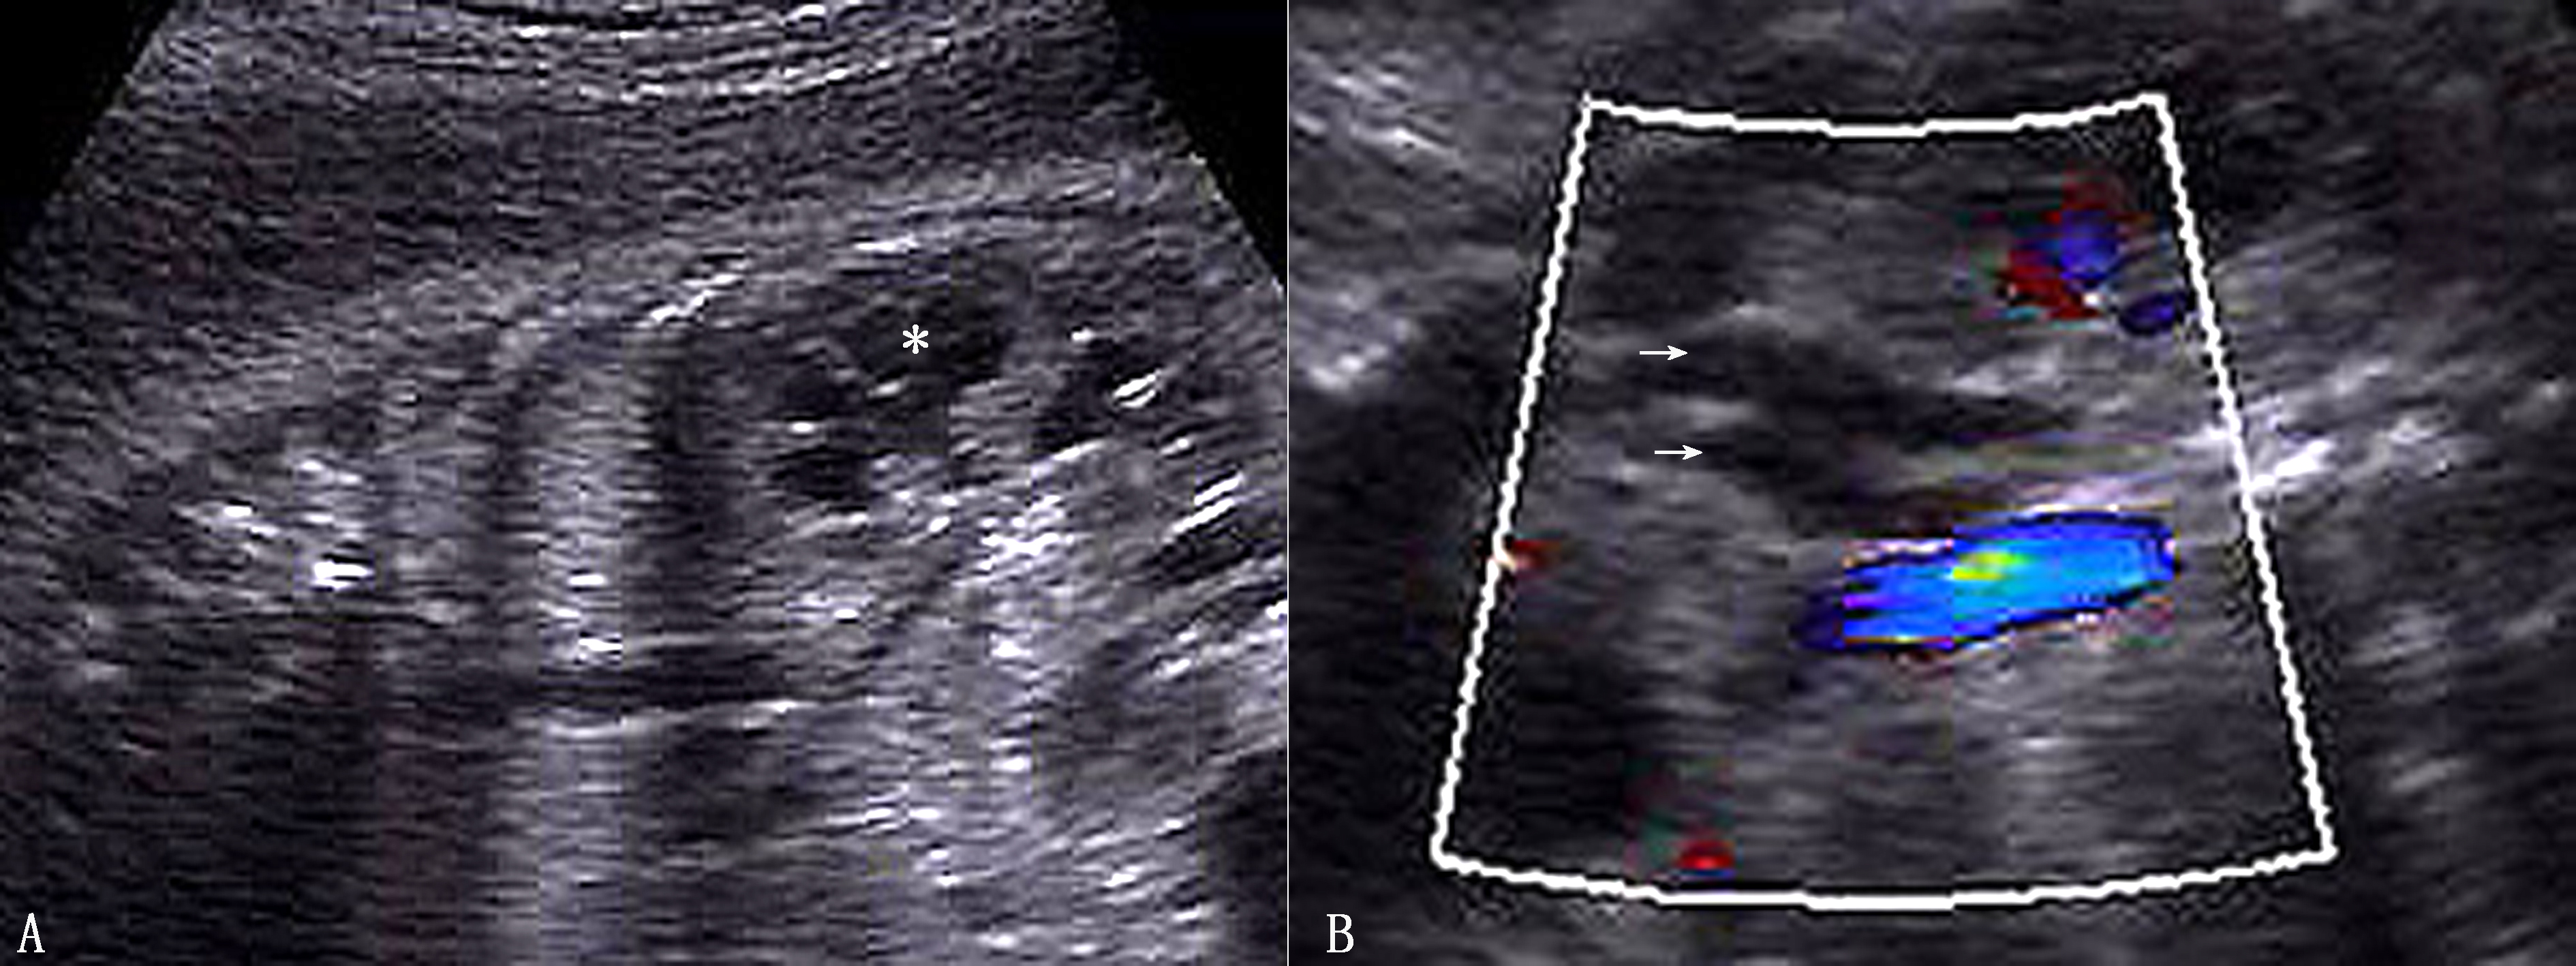

异位肾超声表现为一侧肾区正常肾脏未显示,同侧肾上腺呈“平卧征”,对侧肾脏较大。盆腔内异位时表现为盆腔内毗邻膀胱肾脏样或一实质性回声(图2A),盆腔异位肾发育不良或有肾积水、多囊性发育不良时,有其相应的表现。交叉异位肾对侧肾脏明显增大,常呈分叶状,多为下极融合,也可表现为完全独立的两个肾脏图像,多位于右侧(图2B),可显示两组集合系统图像。胸腔异位肾极少见,在胸腔纵隔内检出肾脏图像而正常腰部肾床区又无肾脏时,应考虑本病的可能。

图2A:孕20周胎儿肾脏(*)异位至盆腔;B:孕26周胎儿肾脏(R-K2)异位至右侧盆腔